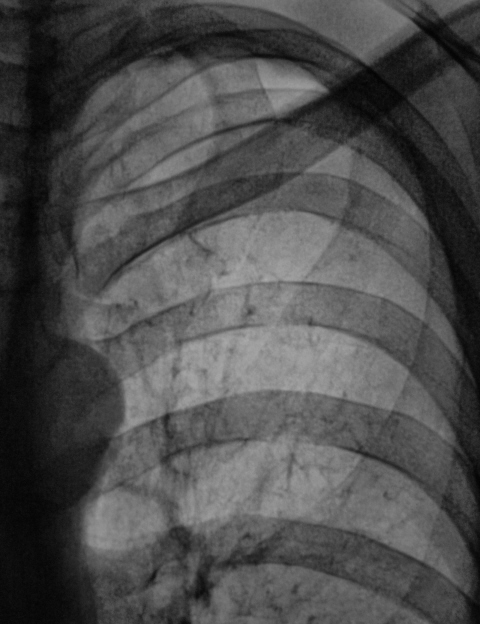

При расшифровке цифровых флюорограмм пациент "взят на контроль". Внушила подозрения правая верхушка.

Представлена флюорограмма в прямой проекции и её фрагменты с разной степенью обработки. Данный снимок "первый", в базе данных предыдущих снимков нет. У нас на стационарном флюорографе ранее не обследовался. Профилактическую флюорографию "проходил" на "передвижке".

Валентин Львович! Уважаемые коллеги! Позволю себе высказать свое мнение. Пациент проходит ФЛГ перед поступлением на работу. Т.е. клиники нет. На фоне полного здоровья выявлены изменения в верхушке справа. Легочной рисунок в верхушке справа усилен, деформирован за счет пневмосклероза, пневмофиброза, что подтверждается данными рентгенологического и КТ исследования. Очаги уплотнения легочной ткани там же. Считаю, что в настоящее время судить об активности процесса не представляется возможным. Тем более, что рентгенархив отсутствует. Никогда не встречал пневмофиброза после банальной пневмонии (в худшем случае-пневмосклероз). Только после массивных, тяжело текущих пневмониях. При этом пневмония занимала не один сегмент, а целые доли. Считаю, что пациента нельзя допускать к работе в детском коллективе, особенно учитывая ситуацию по tbc в Белгородской области. Пациента поставить на учет у фтизиатра и наблюдать. Только после этого можно говорить об активности или отсутствии специфического процесса у пациента.